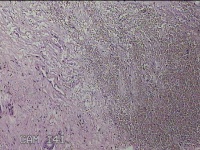

左手指结节

性别

男

年龄

42岁

临床诊断

皮下结节

一般病史

发现左手指结节2个月余。

标本名称

大体所见

灰白粉红色组织1x0.8x0.3cm一块,表面带梭形皮肤1x0.7cm,皮下见结节1x0.8cm,切开皮肤呈实性,切面灰白粉红色,质软。

图片无诊断价值。